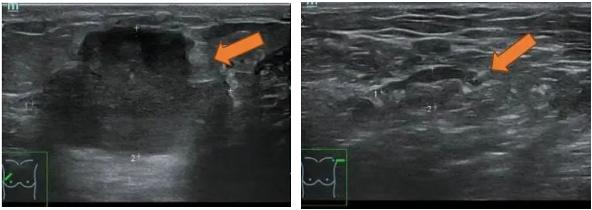

2021.6.28乳腺超声示: 右乳外上象限实性肿块,考虑乳腺癌(BI-RADS-5类)。

右乳10点方向腺体层探及一实质低回声肿块,大小约35.1×22.6mm,内部回声不均匀,其内可探及多个点状强回声,边界不清,形态不规则,周边可见毛刺征,CDFI、CDE示其内血供丰富。右侧腋窝探及多个实质低回声结节,大者约10.2×5.2mm,皮质稍增宽,CDFI、CDE示其内血供不丰富。

图1. 乳腺超声

(2 cycle 后)2021.8.31 乳腺超声示:右乳10点实性肿块 44.9mm×13.1mm。

图5. 乳腺超声